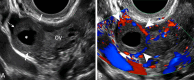

The Society of Radiologists in Ultrasound convened a multisociety panel to develop a first-trimester US lexicon based on scientific evidence, societal guidelines, and expert consensus that would be appropriate for imagers, clinicians, and patients. Through a modified Delphi process with consensus of at least 80%, agreement was reached for preferred terms, synonyms, and terms to avoid. An intrauterine pregnancy (IUP) is defined as a pregnancy implanted in a normal location within the uterus. In contrast, an ectopic pregnancy (EP) is any pregnancy implanted in an abnormal location, whether extrauterine or intrauterine, thus categorizing cesarean scar implantations as EPs. The term pregnancy of unknown location is used in the setting of a pregnant patient without evidence of a definite or probable IUP or EP at transvaginal US. Since cardiac development is a gradual process and cardiac chambers are not fully formed in the first trimester, the term cardiac activity is recommended in lieu of 'heart motion' or 'heartbeat.' The terms 'living' and 'viable' should also be avoided in the first trimester. 'Pregnancy failure' is replaced by early pregnancy loss (EPL). When paired with various modifiers, EPL is used to describe a pregnancy in the first trimester that may or will not progress, is in the process of expulsion, or has either incompletely or completely passed. © RSNA and Elsevier, 2024 Supplemental material is available for this article. This article is a simultaneous joint publication in Radiology and American Journal of Obstetrics & Gynecology. All rights reserved. The articles are identical except for minor stylistic and spelling differences in keeping with each journal's style. Either version may be used in citing this article. See also the editorial by Scoutt and Norton in this issue.